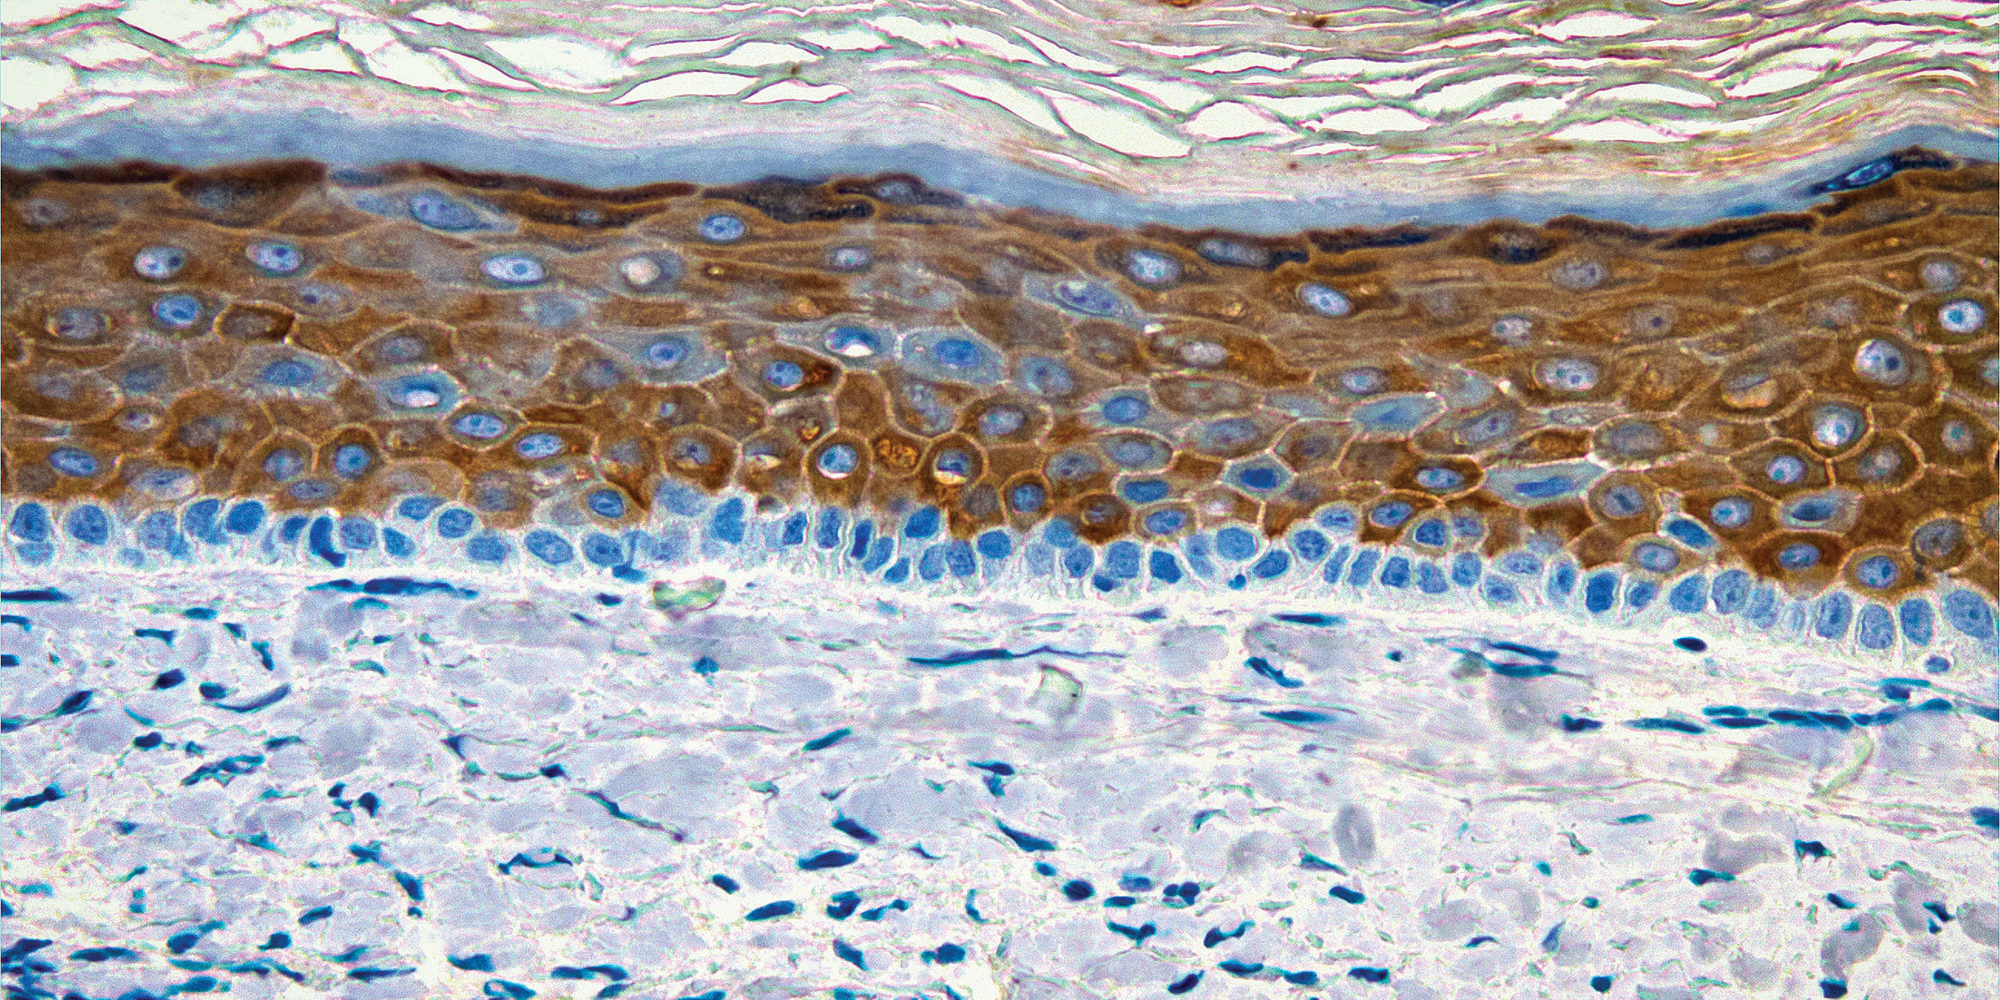

La investigación conjunta de Care Creations® de BASF y CTIBiotech está a punto de alcanzar un nuevo hito. Los socios de la cooperación anuncian el desarrollo de los primeros modelos de piel bioimpresa en 3D, incluidos los macrófagos inmunes. Los modelos de tejidos reconstruidos serán la base para el desarrollo y la prueba de bioactivos destinados a aplicaciones en el cuidado de la piel.

El uso de la tecnología de bioimpresión en 3D de CTIBiotech permitirá a los científicos de BASF aumentar su cartera de modelos de piel bioimpresa en 3D. La tecnología proporcionará una plataforma poderosa para los investigadores del cuidado de la piel que deseen estudiar la función de los macrófagos en una piel totalmente reconstruida.

Los macrófagos supervisan constantemente el microambiente de la piel para detectar indicios de estrés celular, lesión o infección tisular. Son esenciales para cicatrizar las heridas y regenerar completamente el tejido. Con el fin de mantener la homeostasis de la piel, los macrófagos tienen un alto grado de plasticidad que promueve o suprime la inflamación.